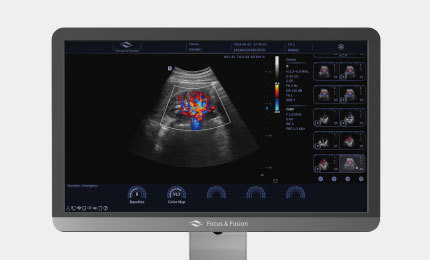

Ultradźwiękowy system diagnostyczny

Mądry i efektowny

Danus